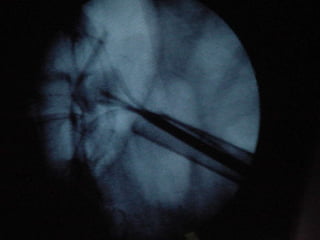

O documento discute o tratamento de urolitíase, especificamente a remoção de cálculos renais através de nefrolitotripsia. A cirurgia aberta é agora muito restrita devido aos avanços da ESWL e procedimentos endourológicos menos invasivos como ureteroscopia e cirurgia percutânea. A cirurgia laparoscópica está substituindo a cirurgia aberta como técnica menos invasiva que combina a tecnologia endourológica com a laparoscópica preservando